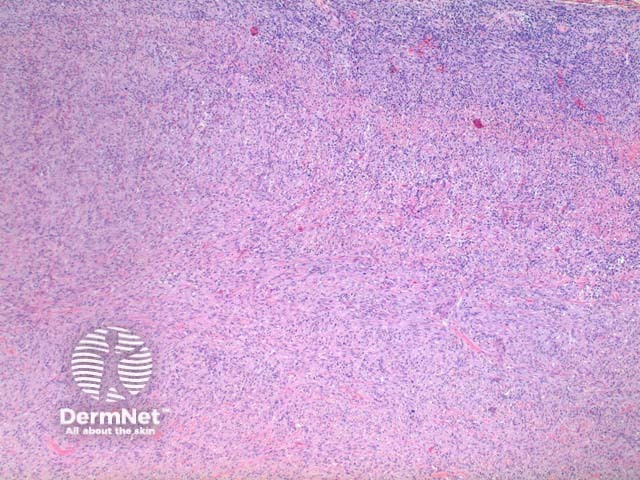

Scanning power view of histology of leiomyosarcoma shows a poorly circumscribed tumour nodule which may be dermal based in the less common dermal leiomyosarcoma (Figure 1) or deeply infiltrating in the subcutaneous form. The tumour is comprised of a spindle cell proliferation forming rough bundles and fascicles (Figures 2 and 3). High power demonstrates spindle cells with cigar shaped nuclei with prominent cytologic atypia and mitotic figures (Figures 4 and 5).

Figure 2